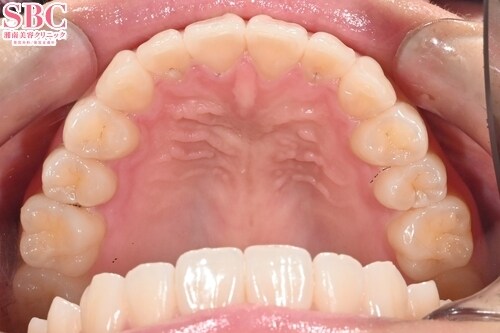

施術前

施術後8ヶ月後

インビザラインGOの症例です。20枚のマウスピースで美しくなられました。下のアーチラインが美しくなられました。マウスピース矯正は医師の設計とお客様が装着時間をお守りいただくことで良い結果が得られます。お客様、マウスピース矯正お疲れ様でした^^

インビザラインGOの症例です。

20枚のマウスピースで美しくなられました。

下のアーチラインが美しくなられました。

マウスピース矯正は医師の設計とお客様が装着時間をお守りいただくことで

良い結果が得られます。

お客様、マウスピース矯正お疲れ様でした^^